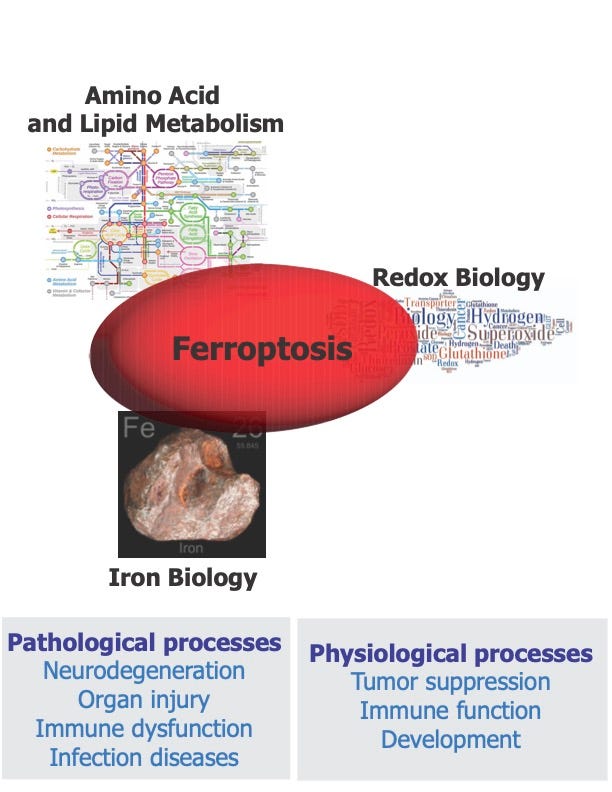

Wan did his postdoctoral training in my lab some years, so I know him well. In his new paper, he reports that mouse motor neurons generated in the laboratory are sensitive to ferroptosis, a form of iron-dependent cell death that we discovered and named in my lab a decade ago.

However, when Wan’s team tested another way of triggering ferroptosis — inhibiting the lipid repair enzyme GPX4 — they found that did indeed trigger ferroptosis in these motor neurons. GPX4 normally restrains ferroptosis by repairing damage to lipids in cell membranes, and loss of this repair mechanism allows that damage to accumulate unchecked.

In summary, the new paper suggests that motor neurons can undergo ferroptosis in response to loss of the GPX4, but not by cysteine deprivation or glutamate toxicity, and that drugs that prevent ferroptosis triggered by loss of GPX4 could potentially help ALS patients. It seems that in motor neurons, the ALS-linked SOD1 mutant doesn’t trigger or drive ferroptosis, but perhaps acts in other cell types.